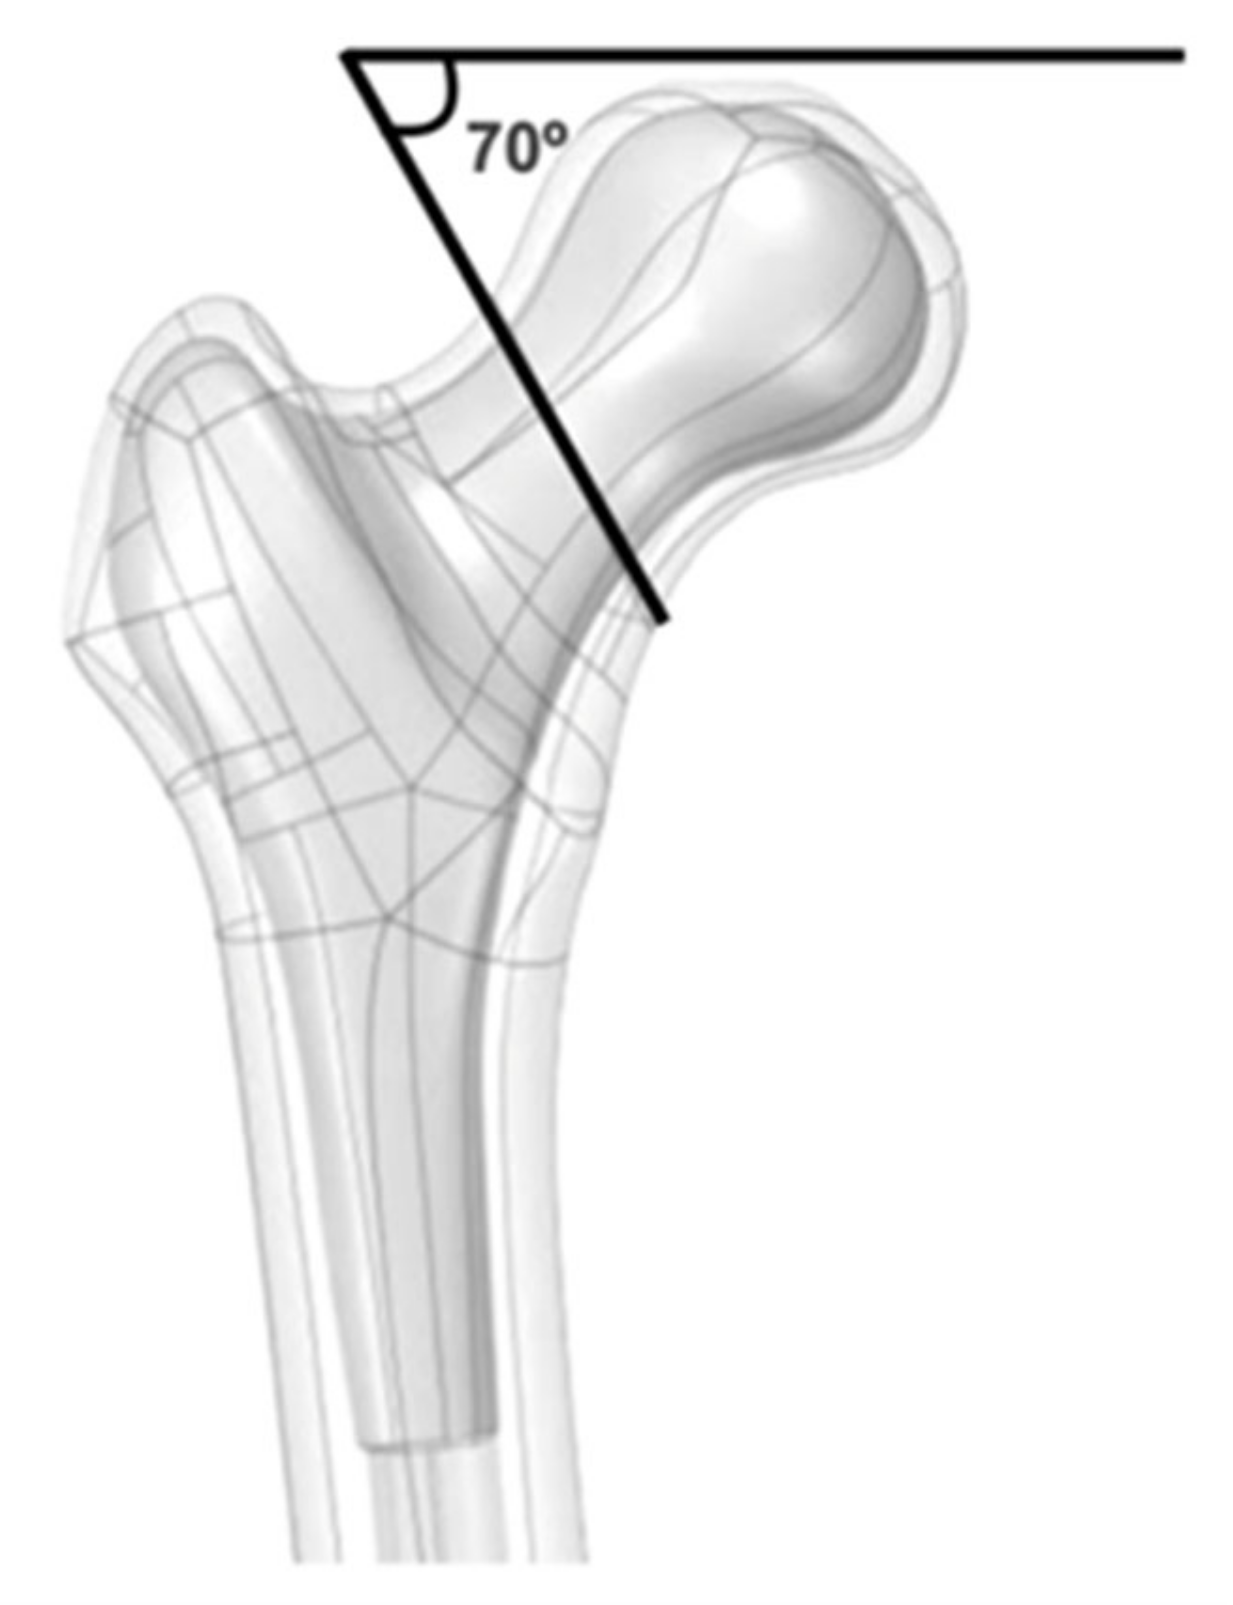

:1. Introduction

2. Materials and Methods